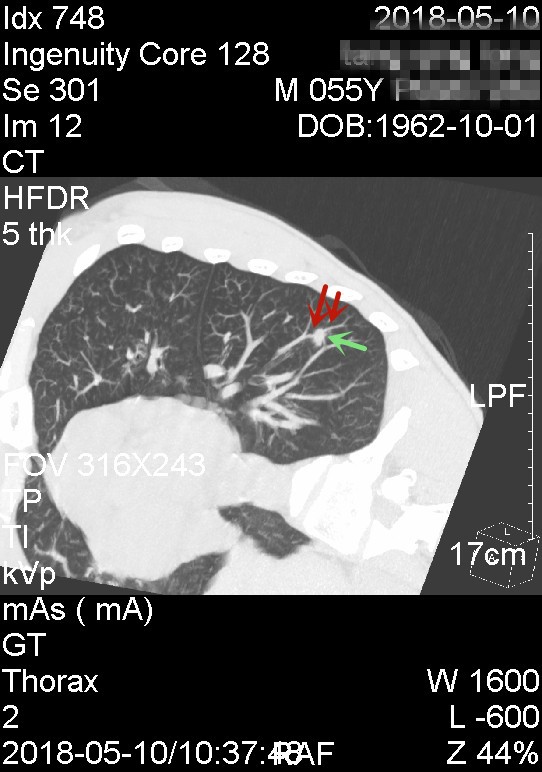

上图红色箭头示血管经过结节后走行略有改变,绝色箭头示有血管进入结节

我们来分析患者左肺结节的特点。首先左肺下叶存在实性结节,直径约1厘米许。其次良性的主要迹象包括:1、结节边缘略显模糊;2、重建图像上看,表面不是非常粗糙,部分区域还是相对光滑;3、血管紧贴结节,不一定完全进入病灶。其中最重要的特征是边缘显模糊。第三,恶性的主要迹象包括:1、表面有浅分叶、凹凸不平;2、血管经过病灶区域受到一定程度牵拉,说明有一定的收缩性;3、上图三绝色箭头示有血管进入结节。